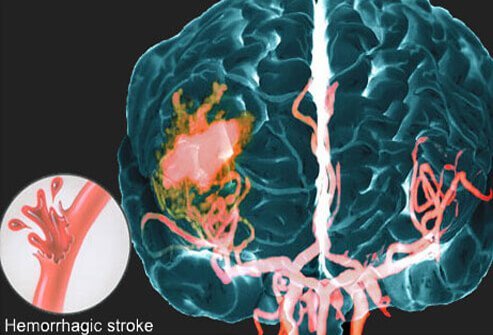

Hemorrhagic Stroke

This picture shows a hemorrhagic stroke using an MRI image. The circle inset outlines what composes a hemorrhagic stroke. A blood vessel in the brain breaks open, and blood escapes into the brain under pressure, compressing other blood vessels and brain cells causing damage and death. This bleeding into the brain is difficult to stop and is more likely to be fatal. There are two types of hemorrhagic strokes: intracerebral and subarachnoid.

Intracerebral Stroke

“Intracerebral” means “within the brain,” and it refers to a stroke caused by a diseased blood vessel bursting within the brain. Intracerebral strokes are usually caused by high blood pressure.

Subarachnoid Stroke

A subarachnoid hemorrhage refers to bleeding immediately surrounding the brain in the area of the head called the subarachnoid space. The main symptom of a subarachnoid stroke is a sudden, severe headache, possibly following a popping or snapping feeling. Many factors can cause a subarachnoid stroke, including head injury, blood thinners, bleeding disorders and bleeding from a tangle of blood vessels known as an arteriovenous malformation.